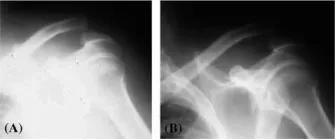

Figure 2 (A) There is a grade III acromioclavicular joint separation (arrow). (B) There is a grade III acromioclavicular joint separation.

There are three grades of separation of the acromioclavicular joint: grade I, with a 50% overlap; grade II, no overlap, but no upward displacement; and grade III, with at least 1 cm of upward displacement of the distal clavicle (Fig. 2A, B).

Grade III implies that there are complete tears of the collateral ligaments of the joint, as well as a tear of the coracoclavicular ligament. In grade I injuries, it is customary to x-ray both sides on the same film (the other, normal, side for comparison) and to take a film with and without the patient carrying a 10-lb weight in each hand, which exaggerates any acromioclavicular separation that may be present.